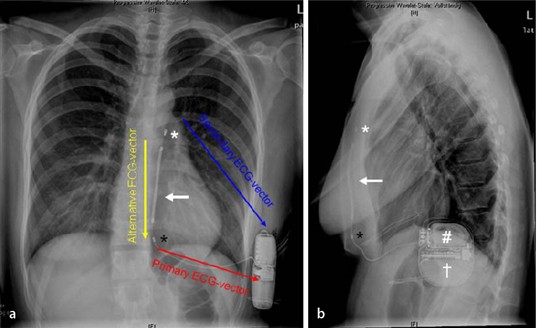

Pdf A Hybrid Defibrillator Implantation Approach In A Patient With Eisenmenger Syndrome Aborted Sudden Cardiac Death And Symptomatic Bradyarrhythmia